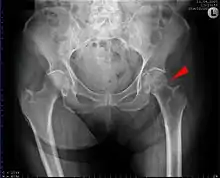

X-rays of the affected hip usually make the diagnosis obvious; AP (anteroposterior) and lateral views should be obtained.

Trochanteric fractures are subdivided into either intertrochanteric (between the greater and lesser trochanter[18]) or pertrochanteric (through the trochanters[18][19]) by the Müller AO Classification of fractures.[20] Practically, the difference between these types is minor. The terms are often used synonymously.[21][22] An isolated trochanteric fracture involves one of the trochanters without going through the anatomical axis of the femur, and may occur in young individuals due to forceful muscle contraction.[23] Yet, an isolated trochanteric fracture may not be regarded as a true hip fracture because it is not cross-sectional.